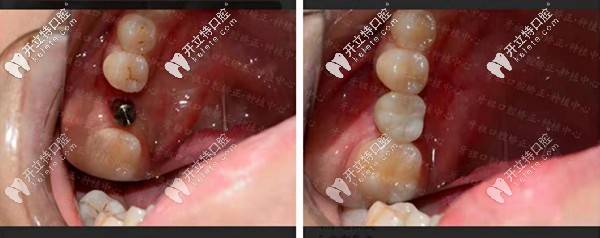

【種植牙案例一】單顆種植牙修復(fù),還原咬合力!

長沙牙祖口腔周磊種植案例一

顧客情況:女性,19歲,右下6號牙殘根不能保留。

種植方案:拔除殘根牙后做種植處理。

種植周期:3個月